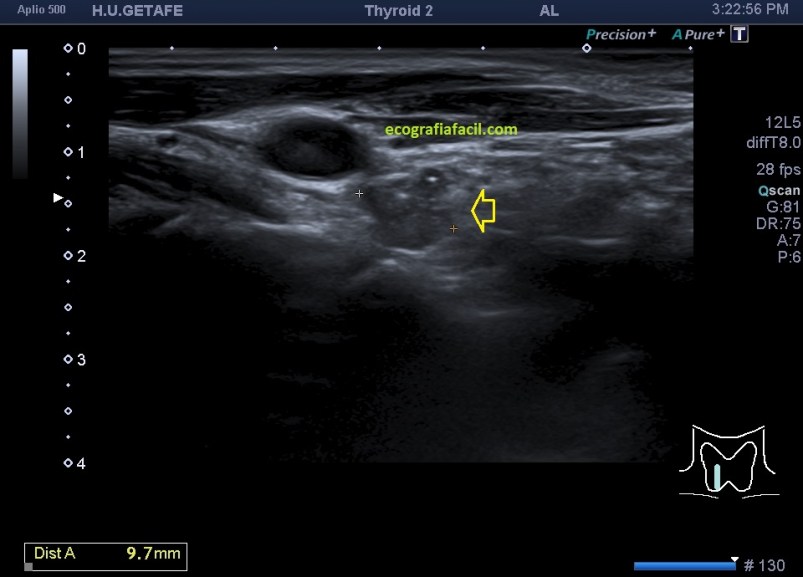

Cuando realizamos este estudio, lo hacemos a modo de control según protocolos de los especialistas de endocrinología ya sea por simple control o por sospecha de recidivas en sus despitajes con analíticas y otras pruebas. Me quiero parar en este último punto, ya que hoy lo que hoy quiero mostrarte el caso de una mujer que ronda los 40 años y a la que le vi esto en la eco tiroidea solicitada por su especialista, mira (flecha amarilla):

La flecha amarilla señala un hallazgo anormal, una vez localizado, protocolo habitual con medidas, doppler, zoom si fuera necesario, documentando bien todo.

Una vez conocida la normalidad relativa de esta arquitectura anatómica volvemos al hallazgo, que como puedes comprobar tiene aspecto nodular, hipoecogénico, de bordes mal definidos y eventualmente, como es el caso de la imagen siguiente (corte longitudinal), tiene microcalcificaciones, semiología ésta de altísimo grado de sospecha.